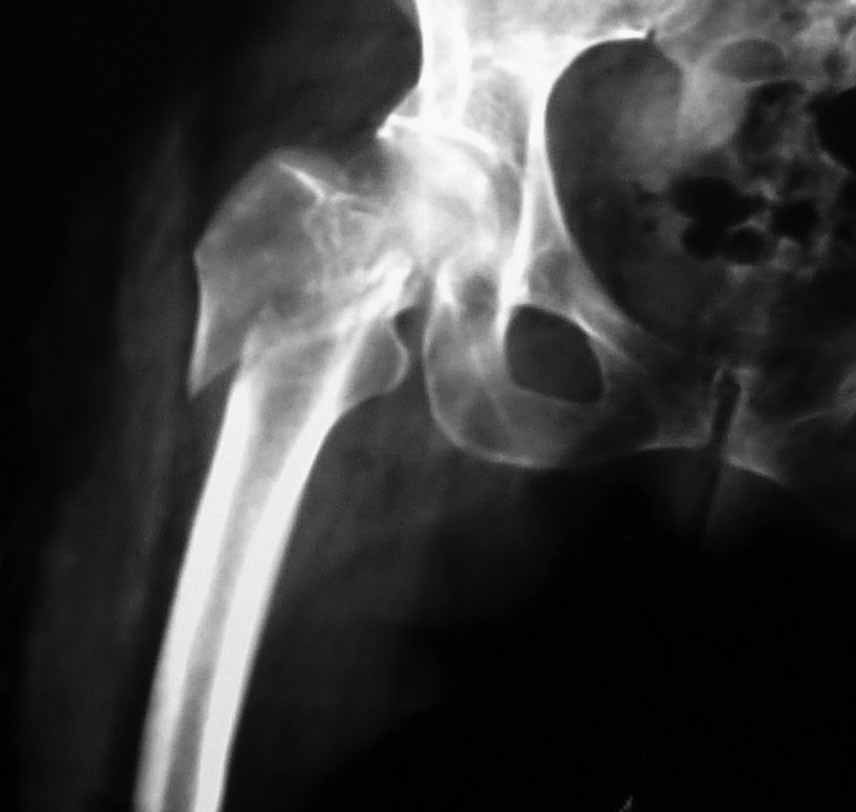

Пациентка 53 лет. ДТП 09.01.12: сочетанная травма: перелом 2-5 ребер справа, ушиб легких;

перелом обеих лонных костей без смещения; закрытый перелом проксимального конца правой

Бедро одномоментно делать не стал, не было уверенности в наличии перелома на уровне шейки. Во время операции смотрел тазобедренный сустав под ЭОПом,

головка неподвижна. После операции повторили КТ, стало очевидно, что имеется субкапитальный перелом. Что делать, остесинтез или протезирование? Если остеосинтез, то чем? Заранее благодарен за советы.